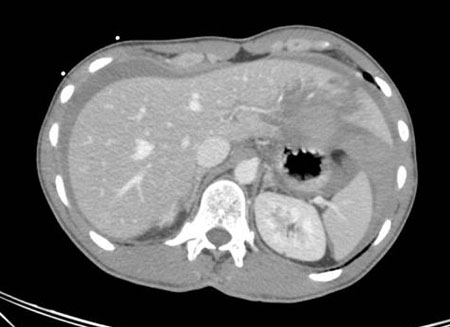

Exploración por TC que muestra laceración hepática

Colección del MetroHealth Medical Center